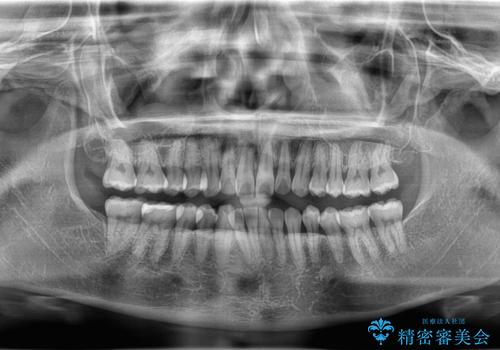

- 「下の前歯が斜めになっている」を主訴に来院された患者様です。

下顎前歯に叢生があり、右上2は反対咬合の状態でした。

昔から食いしばりがあるのを患者様が自覚されており、そのせいか口が開けにくいことも悩まれていました。

抜歯は行わずインビザラインで治療を行いました。